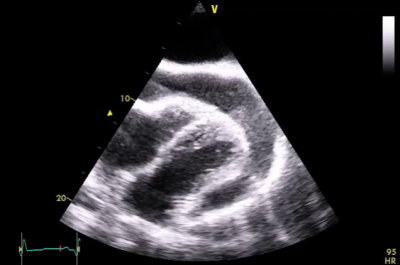

V rámci diferenciální diagnostiky byla provedena perikardiocentéza a vypunktováno 500 ml sangvinolentního výpotku charakteru exsudátu. Pro podezření na akutní perikarditidu byla zahájena terapie nesteroidními antiflogistiky (NSA) a kolchicinem. V případě pleurální tekutiny se jednalo o transudát, ascites měl pak makroskopicky vzhled transudátu, avšak vysokou celkovou bílkovinou (45,1 g/l). Ve všech případech nebyly v punktátech zachyceny onkologicky suspektní elementy, negativní bylo i mikrobiologické vyšetření včetně průkazu TBC. Na kontrolním TTE po punkci byla popsána jako jediná patologie dilatace dolní duté žíly (DDŽ) s minimální respiračním kolapsem. V rámci vyloučení možného onkologické procesu byla doplněna kolonoskopie, ezofagogastroskopie včetně endosonografie (EUS) pankreatu a výpočetní tomografie (CT) hrudníku a břicha, vše s negativním nálezem. Na základě výsledků UZ a elastografie jater byla na prvním místě jako základní onemocnění zvažována jaterní cirhóza, ačkoliv na CT břicha byl přítomen pouze obraz jaterní kongesce bez typických známek pro cirhózu. Ke stávající protizánětlivé terapii byla proto přidána diuretika (furosemid + spironolacton) a pacient byl předán k ambulantnímu sledování do gastroenterologické ambulance, kde došlo k postupnému vysazení protizánětlivé terapie. Dle kontrolní TTE (první vyšetření na našem pracovišti), po necelých třech měsících od dimise ze spádové interny, byla diagnostikována recidiva velkého perikardiálního výpotku (video 1), stále trvající dilatace DDŽ a jako vedlejší nález i menší levostranný fluidothorax.

Video 1 – Echokardiografie: velký perikardiální výpotek, maximální diastolická separace 25 mm v oblasti hrotu. Subkostální projekce.Protože nadále probíhalo došetřování suspektního primárního procesu jater, etiologie výpotku byla uzavírána jako sekundární a opětovná protizánětlivá terapie nebyla zahájena. Vzhledem k postupnému zhoršování klinického stavu, sklonu k hypotenzi a další progresi množství tekutiny v perikardu jsme naplánovali v rámci multioborové spolupráce diagnosticko-terapeutickou perikardiocentézu. Iniciálně bylo pod UZ kontrolou z apikálního přístupu vypunktováno 750 ml sangvinolentního exsudátu, avšak dle kontrolního TTE došlo k rychlému doplnění perikardiální tekutiny (video 2).